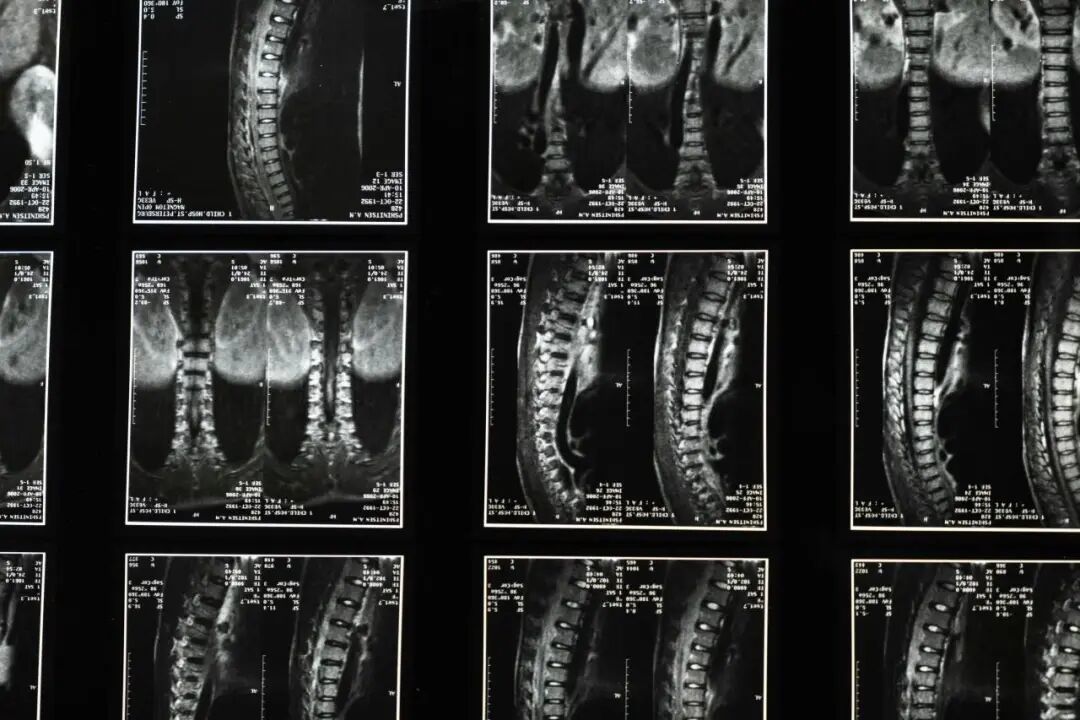

随着影像学检查的普及,“腰椎间盘膨出”这个诊断越来越频繁地出现在体检报告和门诊病历中。很多人看到这个结果,第一反应往往是焦虑和担忧:是不是腰不行了?事实上,腰椎间盘膨出远没有想象中那么可怕。下面为你全面解读这一常见的影像学发现。

腰椎间盘由两部分组成:中央是富有弹性的胶状物质(髓核),外围是坚韧的纤维环。随着年龄增长、日常劳损或不当用力,纤维环可能逐渐变得松弛、弹性下降,导致整个间盘向周围均匀、对称地轻微膨出,就像轮胎轻微鼓包一样,但纤维环并没有破裂,这就是影像报告上所说的“膨出”。

大量研究显示,在没有任何腰痛的成年人中,进行腰椎MRI检查,约有30%~40%的人会显示出不同程度的间盘膨出或突出。这意味着,影像学上的发现不一定等同于疾病,也可能是一种与年龄相关的退行性改变。